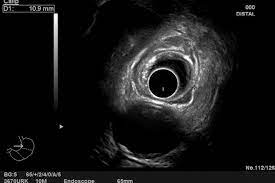

La ecografía endoscópica es un procedimiento que requiere un endoscopio especial con un transductor de ecografía en la punta. Este tipo de endoscopio se llama endoscopio ecográfico o ecoendoscopio. El…